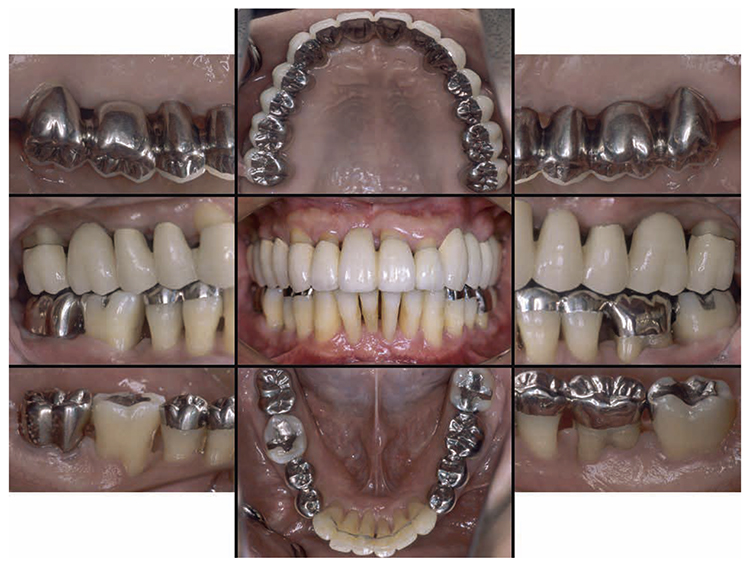

After orthodontic treatment was completed, fabrication of the final prosthesis was started.. Preliminary impression of the maxilla and mandible were taken, anatomic facebow and checkbite were obtained, and prosthetic diagnosis was performed. In the treatment plan before surgery, the first choice for the maxilla was the full mouth bridge that connects all teeth. However, since no parallelism was seen on the anchor teeth, and additionally all teeth were vital teeth, convenient pulpectomy was sought as a possibility. Additionally, in designing treatment for patients with severe periodontitis, to disperse the occlusal load to the entire jaw, which was most important, semi-fixed multi-tooth prosthetic using key and keyway attachment was designed for final prosthetic in this case. After taking parallelism of anchor teeth into consideration, multi-tooth models with attachments were designed for 13 and 14, and for 22 and 23. After deciding on the shape of prosthetics, anchor teeth were formed, impression was taken, and subsequently final confirmation was made on accurate fit with coping trial. After final prosthetic treatment on the maxilla, prosthetics were placed on the mandible starting with 47. Since metal crowns were placed on both 47 and 36, onlay-type metal crowns were placed on 44, 45, 34 and 35 for occlusal support. After completion of prosthetic treatment on all teeth, confirmation was made with an occlusal force tester (Dental Prescale®,GC, Tokyo) that occlusal force was equally distributed across the entire jaw. Additionally, nighttime bruxism was addressed by producing and applying nightguards since the patient had the habit of clenching.

7) Reevaluation testing (December 2003)

At the reevaluation examination after treatment to restore oral function, the color of gingiva was pink, and with prosthetics, intraoral harmony was replicated esthetically and functionally. (Fig.6a). The average PD across the entire jaw was 2.1mm, maximum PD was 4.0mm, the ratio of PD of 3mm or below was 99.3%, no BOP was found and the condition of the periodontal tissue was stable (Fig.6b). In the X-ray, continuity of the alveolar hard line was replicated and the sequence of bone trabeculae was normal, and therefore, the patient transitioned to the SPT phase (Fig.6c).

(Fig.6a) Intraoral photo after completion of restoration of oral function was completed(2013.4)

(Fig.6c) Digital X-ray 14 after completion of restoration of oral function (April 2013)